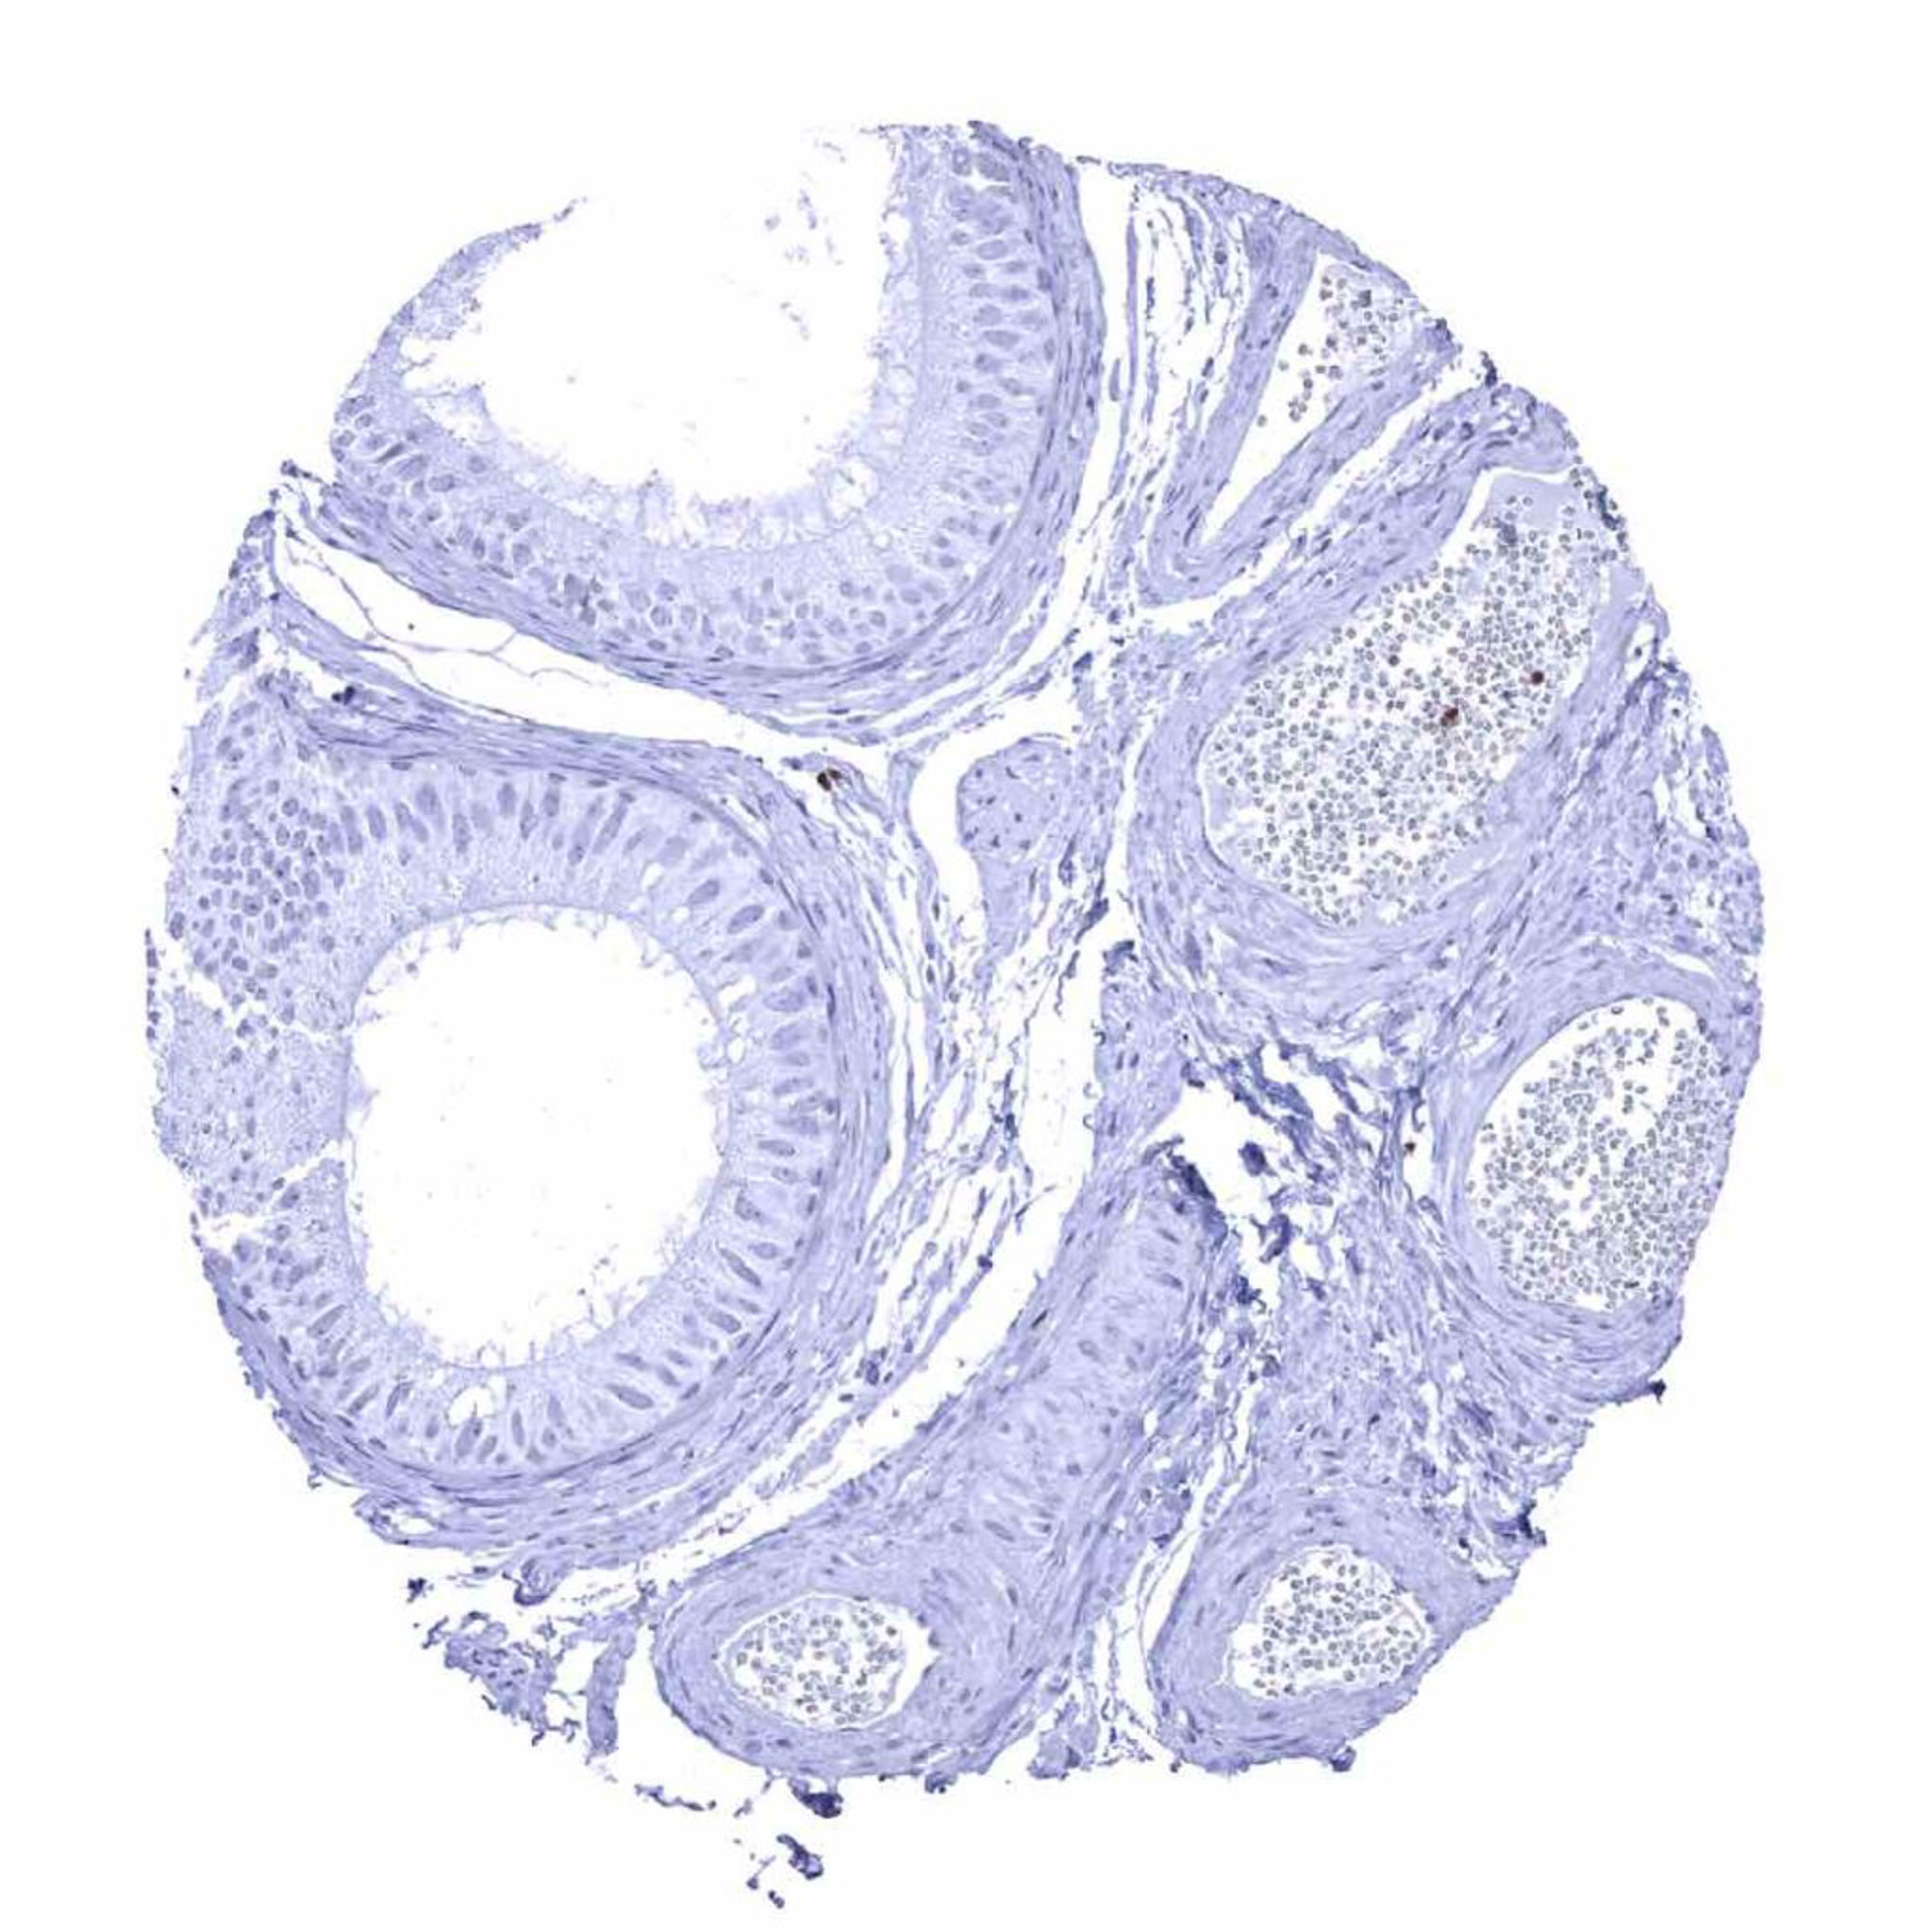

Seminal vesicle – Scattered ZAP70 positive lymphocytes are mainly seen in the epithelium.